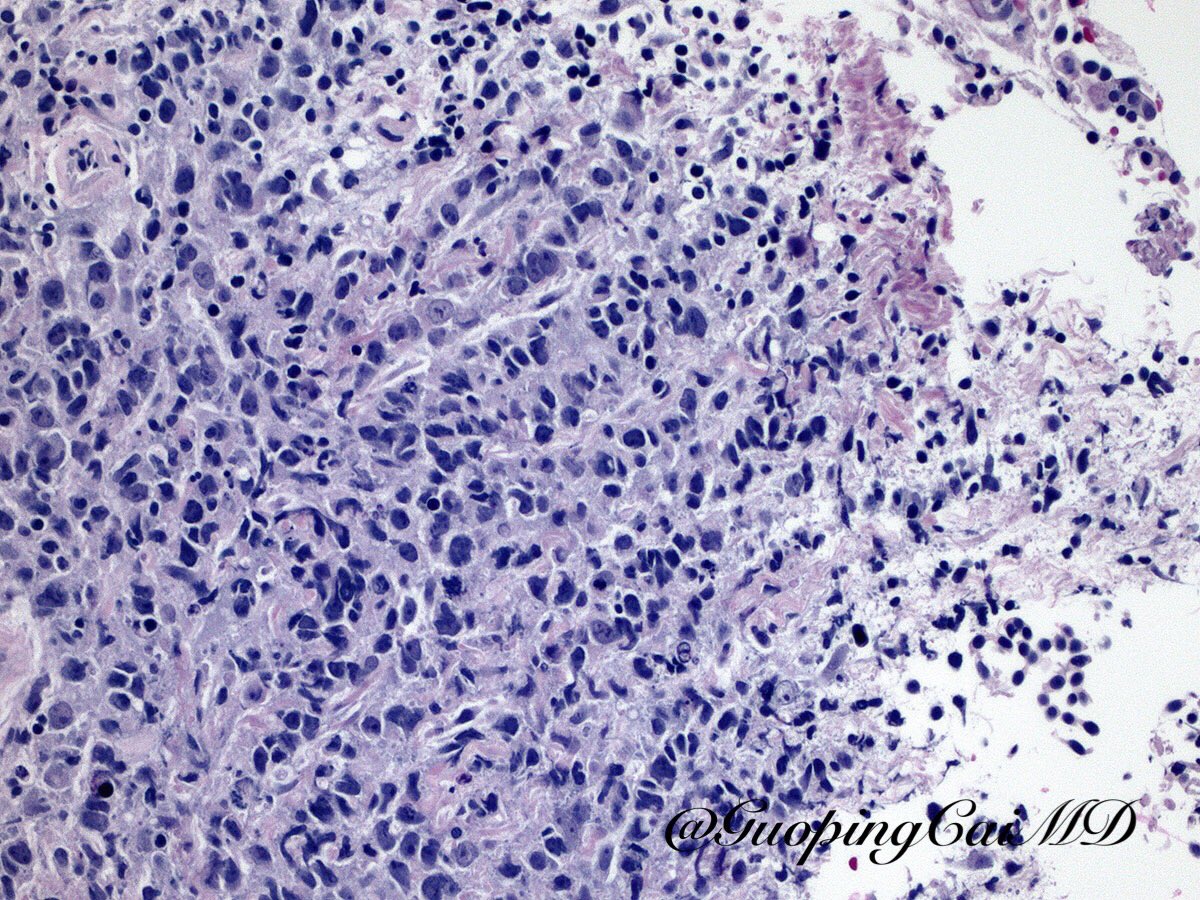

#PathQuiz 🔬🫁 #PulmonaryPath A) Large cell neuroendocrine carcinoma B) Diffuse large B-cell lymphoma C) Small cell lung carcinoma D) Squamous cell carcinoma #Pathology #Cytology #CytoPath #ThoracicPath

DrCycloPath's tweet image. #PathQuiz 🔬🫁 #PulmonaryPath

A) Large cell neuroendocrine carcinoma

B) Diffuse large B-cell lymphoma

C) Small cell lung carcinoma

D) Squamous cell carcinoma

#Pathology #Cytology #CytoPath #ThoracicPath